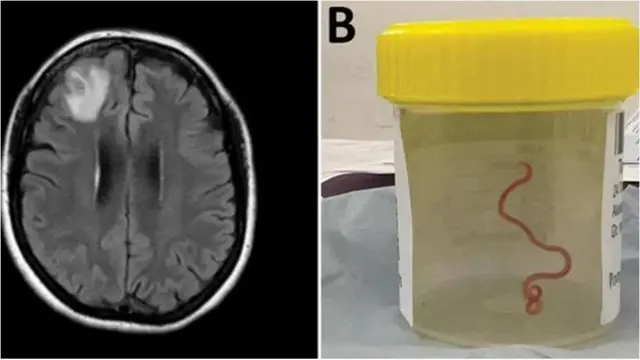

في سابقة هي الأولى من نوعها في العالم، أزال العلماء دودة حية طولها 8 سم من دماغ امرأة أسترالية.

وتم سحب "الهيكل الشبيه بالخيط" من الفص الأمامي التالف للمريضة أثناء الجراحة في كانبيرا العام الماضي، لكن تقرير الجراحة لم يُنشر إلا هذا العام.

تم إدخالها إلى المستشفى في أواخر يناير/كانون الأول 2021، وكشف الفحص لاحقاً عن "آفة غير نمطية داخل الفص الجبهي الأيمن من الدماغ".

لكن سبب حالتها لم يتم الكشف عنه إلا من خلال مشر ط الدكتور باندي أثناء إجراء خزعة في يونيو/حزيران 2022.

وقال الأطباء إن الطفيل الأحمر كان من الممكن أن يبقى على قيد الحياة في دماغها لمدة تصل إلى شهرين.

وأكد الباحثون في مجلة الأمراض المعدية الناشئة التي نشرت هذه الحالة أنه يُعتقد أن حالتها هي أول حالة لغزو اليرقات وتطورها في الدماغ البشري.